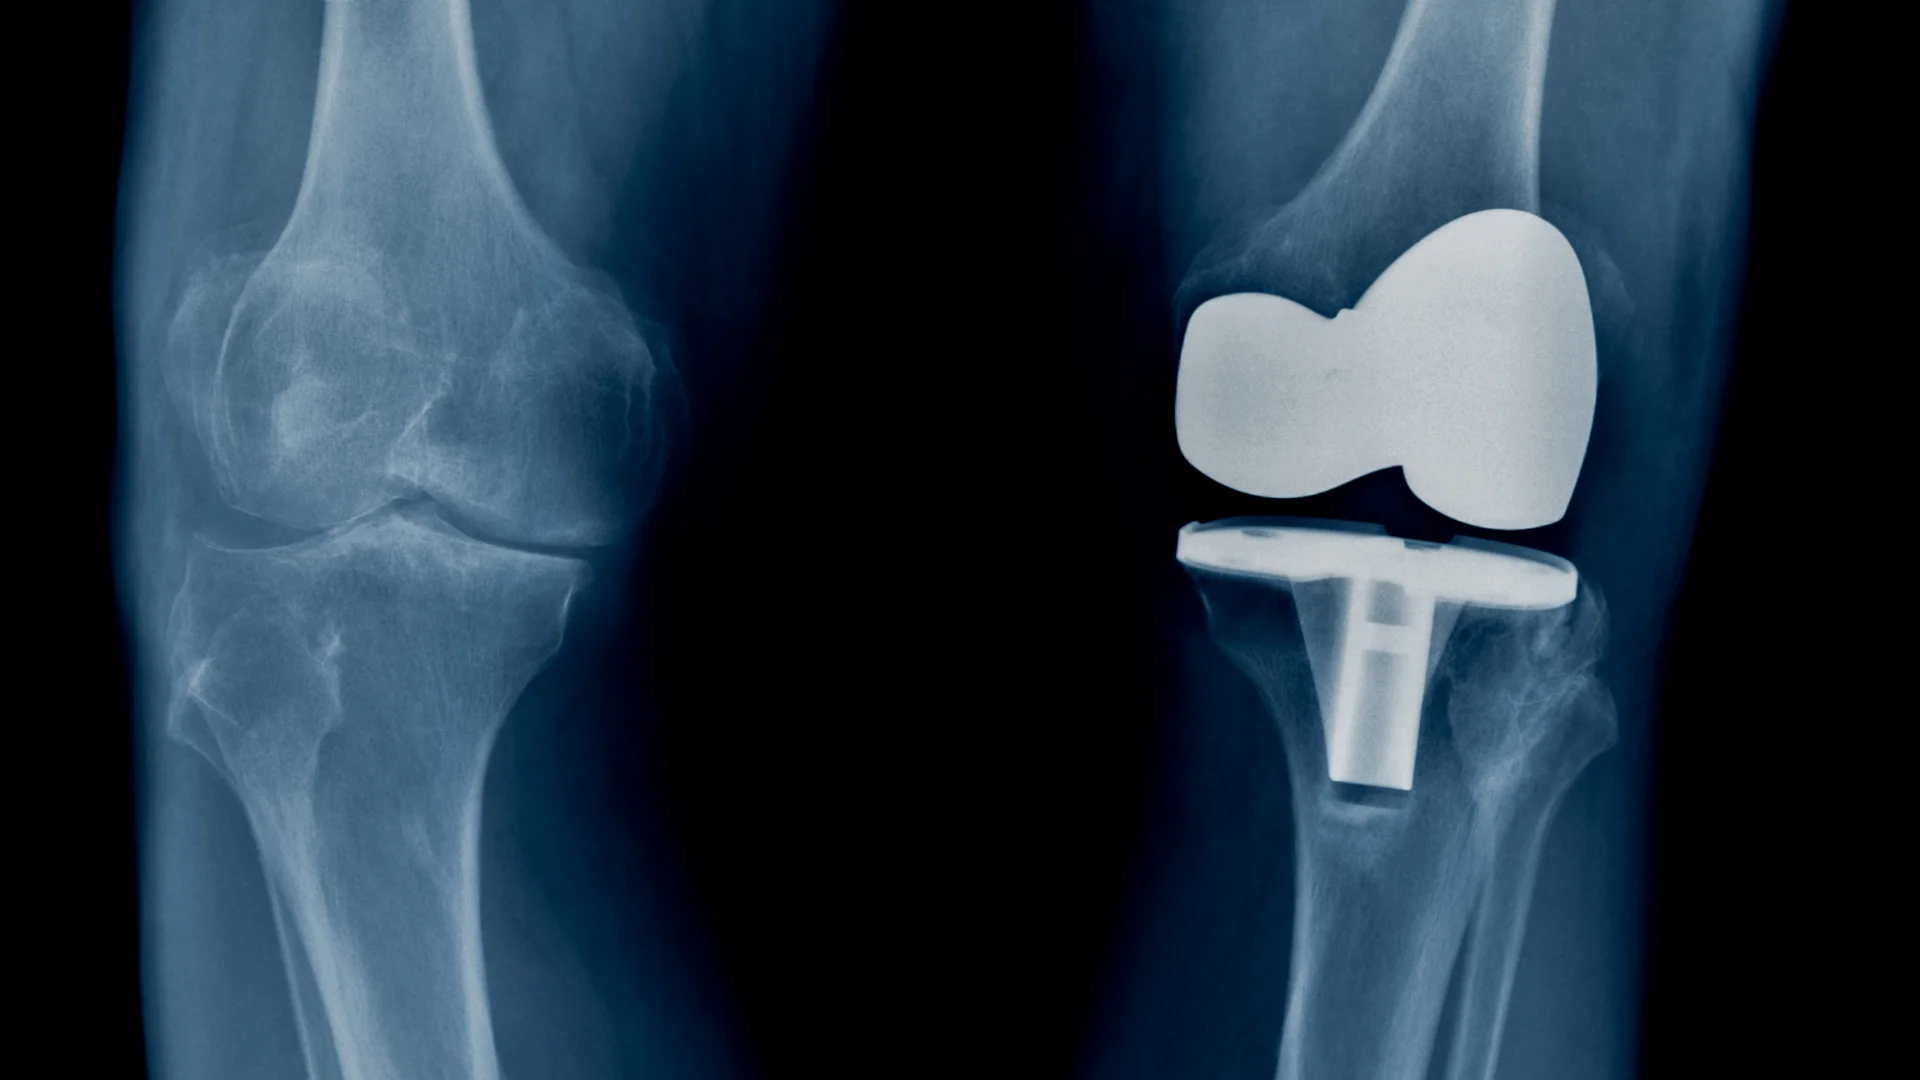

Ендопротезування повертає якість життя, знімає біль і дає можливість рухатися без обмежень. Але жоден імплант не є абсолютно вічним, термін його служби залежить від матеріалів, техніки встановлення і того, як пацієнт поводиться після операції. Розуміння цих факторів допомагає зберегти протез у робочому стані на багато років.

Більшість якісних імплантів працюють 15-20 років, а деякі й довше - понад два десятиліття. Керамічні та поліетиленові пари тертя мають кращу зносостійкість, а сучасні фіксаційні технології додатково підвищують стабільність. У молодих і фізично активних людей протез може зношуватися швидше, тоді як у старших темп зношування повільніший.

Ендопротез починає працювати одразу після встановлення, але інтенсивність навантажень має зростати поступово. Різкі рухи, надмірна вага та травми можуть прискорити зношування. Водночас правильний режим дозволяє імпланту служити дуже довго.